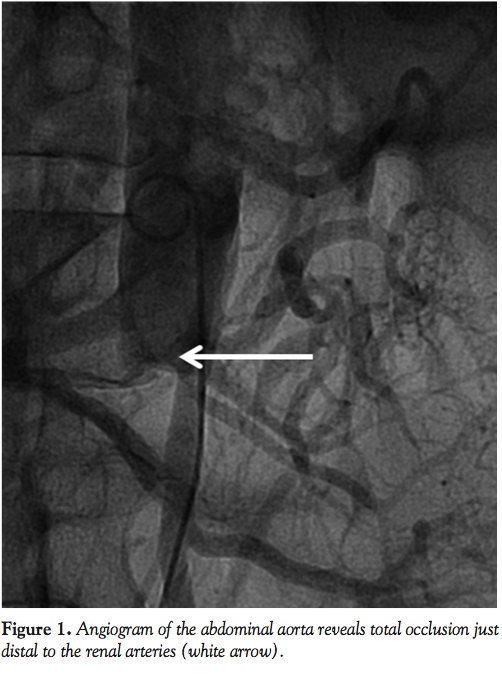

A 69-year-old male presented to our facility 1 year after progressive weakness and pain to his lower extremities that acutely worsened 3 weeks prior to hospitalization. Over this period, the patient had developed significant functional limitations and become bed bound. He had developed multiple ulcers and infected wounds on his buttocks and lower extremities. He had also developed atrophy to his legs with significant loss of motor and sensory function. A computed tomography scan with contrast was of low quality, though suggested occlusion of the infrarenal aorta (Figure 1). As surgical treatment is preferred for this condition, he was evaluated by the vascular surgery department, but he was turned down for surgical intervention due to severe comorbid conditions, including a complicated and prolonged hospital course with urinary tract infections, clostridium dificile colitis, and hospital-acquired pneumonia. The patient was then evaluated by the interventional cardiology department for endovascular treatment of his aortic occlusion. This was thought to help facilitate wound healing and decrease pain. After being informed of the potential risks and benefits, the patient was brought to our cardiac catheterization laboratory for revascularization.